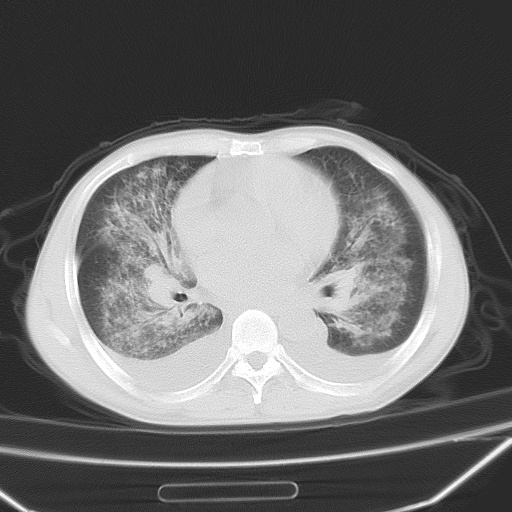

男、42岁、咯血3天。既往有甲亢、贫血、血尿蛋白尿史多年。血象:wbc:6.   中性粒:70.6%。

双肺堆成磨玻璃影,双测胸腔积液。考虑:肺水肿、间质性肺炎、真菌感染、ards、hiv感染、肺出血。

双肺野对称性磨玻璃影,分布于内中带,双侧胸水,患者有咯血。

1、间质性肺水肿;2、结合临床病史及实验室检查,考虑为肺出血肾炎综合征。    此病需与间质性炎症、粟粒性肺结核鉴别。

肺出血-肾炎综合征又称good-pasture综合征,属少见病,近几年国内有散在报告。此病原因未明,目前多数学者认为与自身免疫有关,即病人体内存在抗-gbm抗体,而病人肺毛细血管基底膜与肾小球基底膜有交叉反应性抗原,从而引起肺泡毛细血管基底膜和肾小球基底膜病变,导致肺出血及肾炎表现。血清抗-gbm抗体阳性,或组织活检见沿肾小球和肺泡基底膜有igg沉积,为本病的3个诊断依据。临床上有许多疾病同时表现为肺出血和肾炎,如系统性红斑狼疮、韦格肉芽肿和增殖性肾小球肾炎等,但这些疾病都不同时具备上述三方面的条件

双肺野广泛对称性磨玻璃影、实变影,以肺门为中心,主要分布于内中带,符合典型肺泡性肺水肿;伴双侧胸腔少量游离积液。结合患者既往病史且咯血就诊,支持多因素(尿毒症等)所致之肺水肿、肺出血、胸水;影像表现暂不考虑心源性水肿,且症状也不太符。需密切随诊结合临床治疗等进一步明确。

心影增大密度略低,双肺磨玻璃样高密度影及双侧胸腔积液,考虑心功能不全继发双肺肺水肿及双侧胸腔积液。心影密度略低,考虑贫血所致。